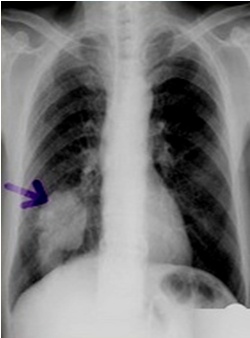

圖中可見右下肺分葉狀腫塊,根據公式診斷周圍型肺癌